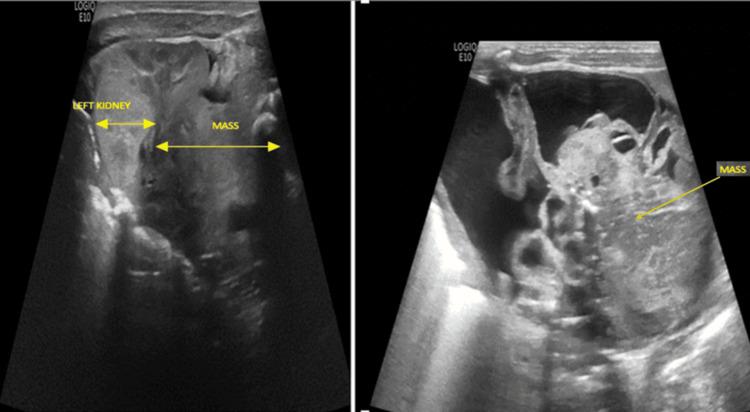

Retroperitoneal teratomas are rare neoplasms in neonates, presenting with nonspecific symptoms and variable clinical features, making diagnosis challenging. Radiological investigations, particularly fetal ultrasound and contrast-enhanced computed tomography, play a critical role in their detection. Differential diagnoses include neuroblastoma, adrenal hemorrhage, and congenital cystic lesions, which share overlapping clinical and imaging features. This case report describes a neonate delivered at 39 weeks of gestation, weighing 2.93 kg, to a 30-year-old gravida 2, para 1 mother with unremarkable serological tests during pregnancy. Fetal ultrasonography performed at 31 weeks, followed by magnetic resonance imaging at 35 weeks, revealed a large, multi-cystic, and solid lesion located above the left kidney. Postnatal physical examination identified a firm, non-tender abdominal mass that was confined to the left side and did not cross the midline. Imaging studies, including abdominal radiographs, ultrasonography, and contrast-enhanced computed tomography, confirmed a large left supra-renal mass. Meta-iodo-benzyl-guanidine scintigraphy combined with single-photon emission computed tomography showed no activity in the mass. Serum alpha-fetoprotein levels were within the normal range for term neonates, and the infant had normal beta-human chorionic gonadotropin and urine homovanillic acid levels. The infant underwent exploratory laparotomy on the sixth postnatal day, confirming an immature teratoma without malignant components. Postoperatively, AFP levels demonstrated the expected physiological decline, consistent with the absence of malignant components. The infant was discharged on postnatal day 35. This case highlights the diagnostic complexities of retroperitoneal teratomas in neonates and underscores the critical role of antenatal ultrasound and a multidisciplinary approach in ensuring effective diagnosis and management.

腹膜后畸胎瘤在新生儿中是罕见的肿瘤,表现为非特异性症状和多样的临床特征,这使得诊断具有挑战性。影像学检查,尤其是胎儿超声和增强计算机断层扫描,在其检测中起着关键作用。鉴别诊断包括神经母细胞瘤、肾上腺出血和先天性囊性病变,它们具有重叠的临床和影像学特征。本病例报告描述了一名孕39周出生、体重2.93千克的新生儿,其母亲为30岁经产妇,孕2产1,孕期血清学检查无异常。孕31周时进行了胎儿超声检查,孕35周时进行了磁共振成像检查,结果显示左肾上方有一个大的多囊实性病变。出生后体格检查发现左侧有一个质地硬、无压痛的腹部肿块,局限于左侧,未越过中线。包括腹部X线平片、超声和增强计算机断层扫描在内的影像学检查证实左肾上腺有一个大肿块。间碘苄胍闪烁显像联合单光子发射计算机断层扫描显示肿块无活性。足月新生儿血清甲胎蛋白水平在正常范围内,婴儿的β-人绒毛膜促性腺激素和尿高香草酸水平正常。婴儿在出生后第6天接受了剖腹探查术,证实为无恶性成分的未成熟畸胎瘤。术后,甲胎蛋白水平呈现预期的生理性下降,这与无恶性成分相符。婴儿于出生后第35天出院。本病例突出了新生儿腹膜后畸胎瘤的诊断复杂性,并强调了产前超声和多学科方法在确保有效诊断和管理中的关键作用。